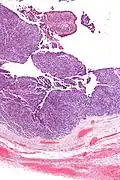

Micrograph of transitional cell carcinoma of the ovary. H&E stain.

TCC of the ovary is diagnosed by examination of the tissue by a pathologist. It has a characteristic appearance under the microscope and distinctive pattern of immunostaining.[2]